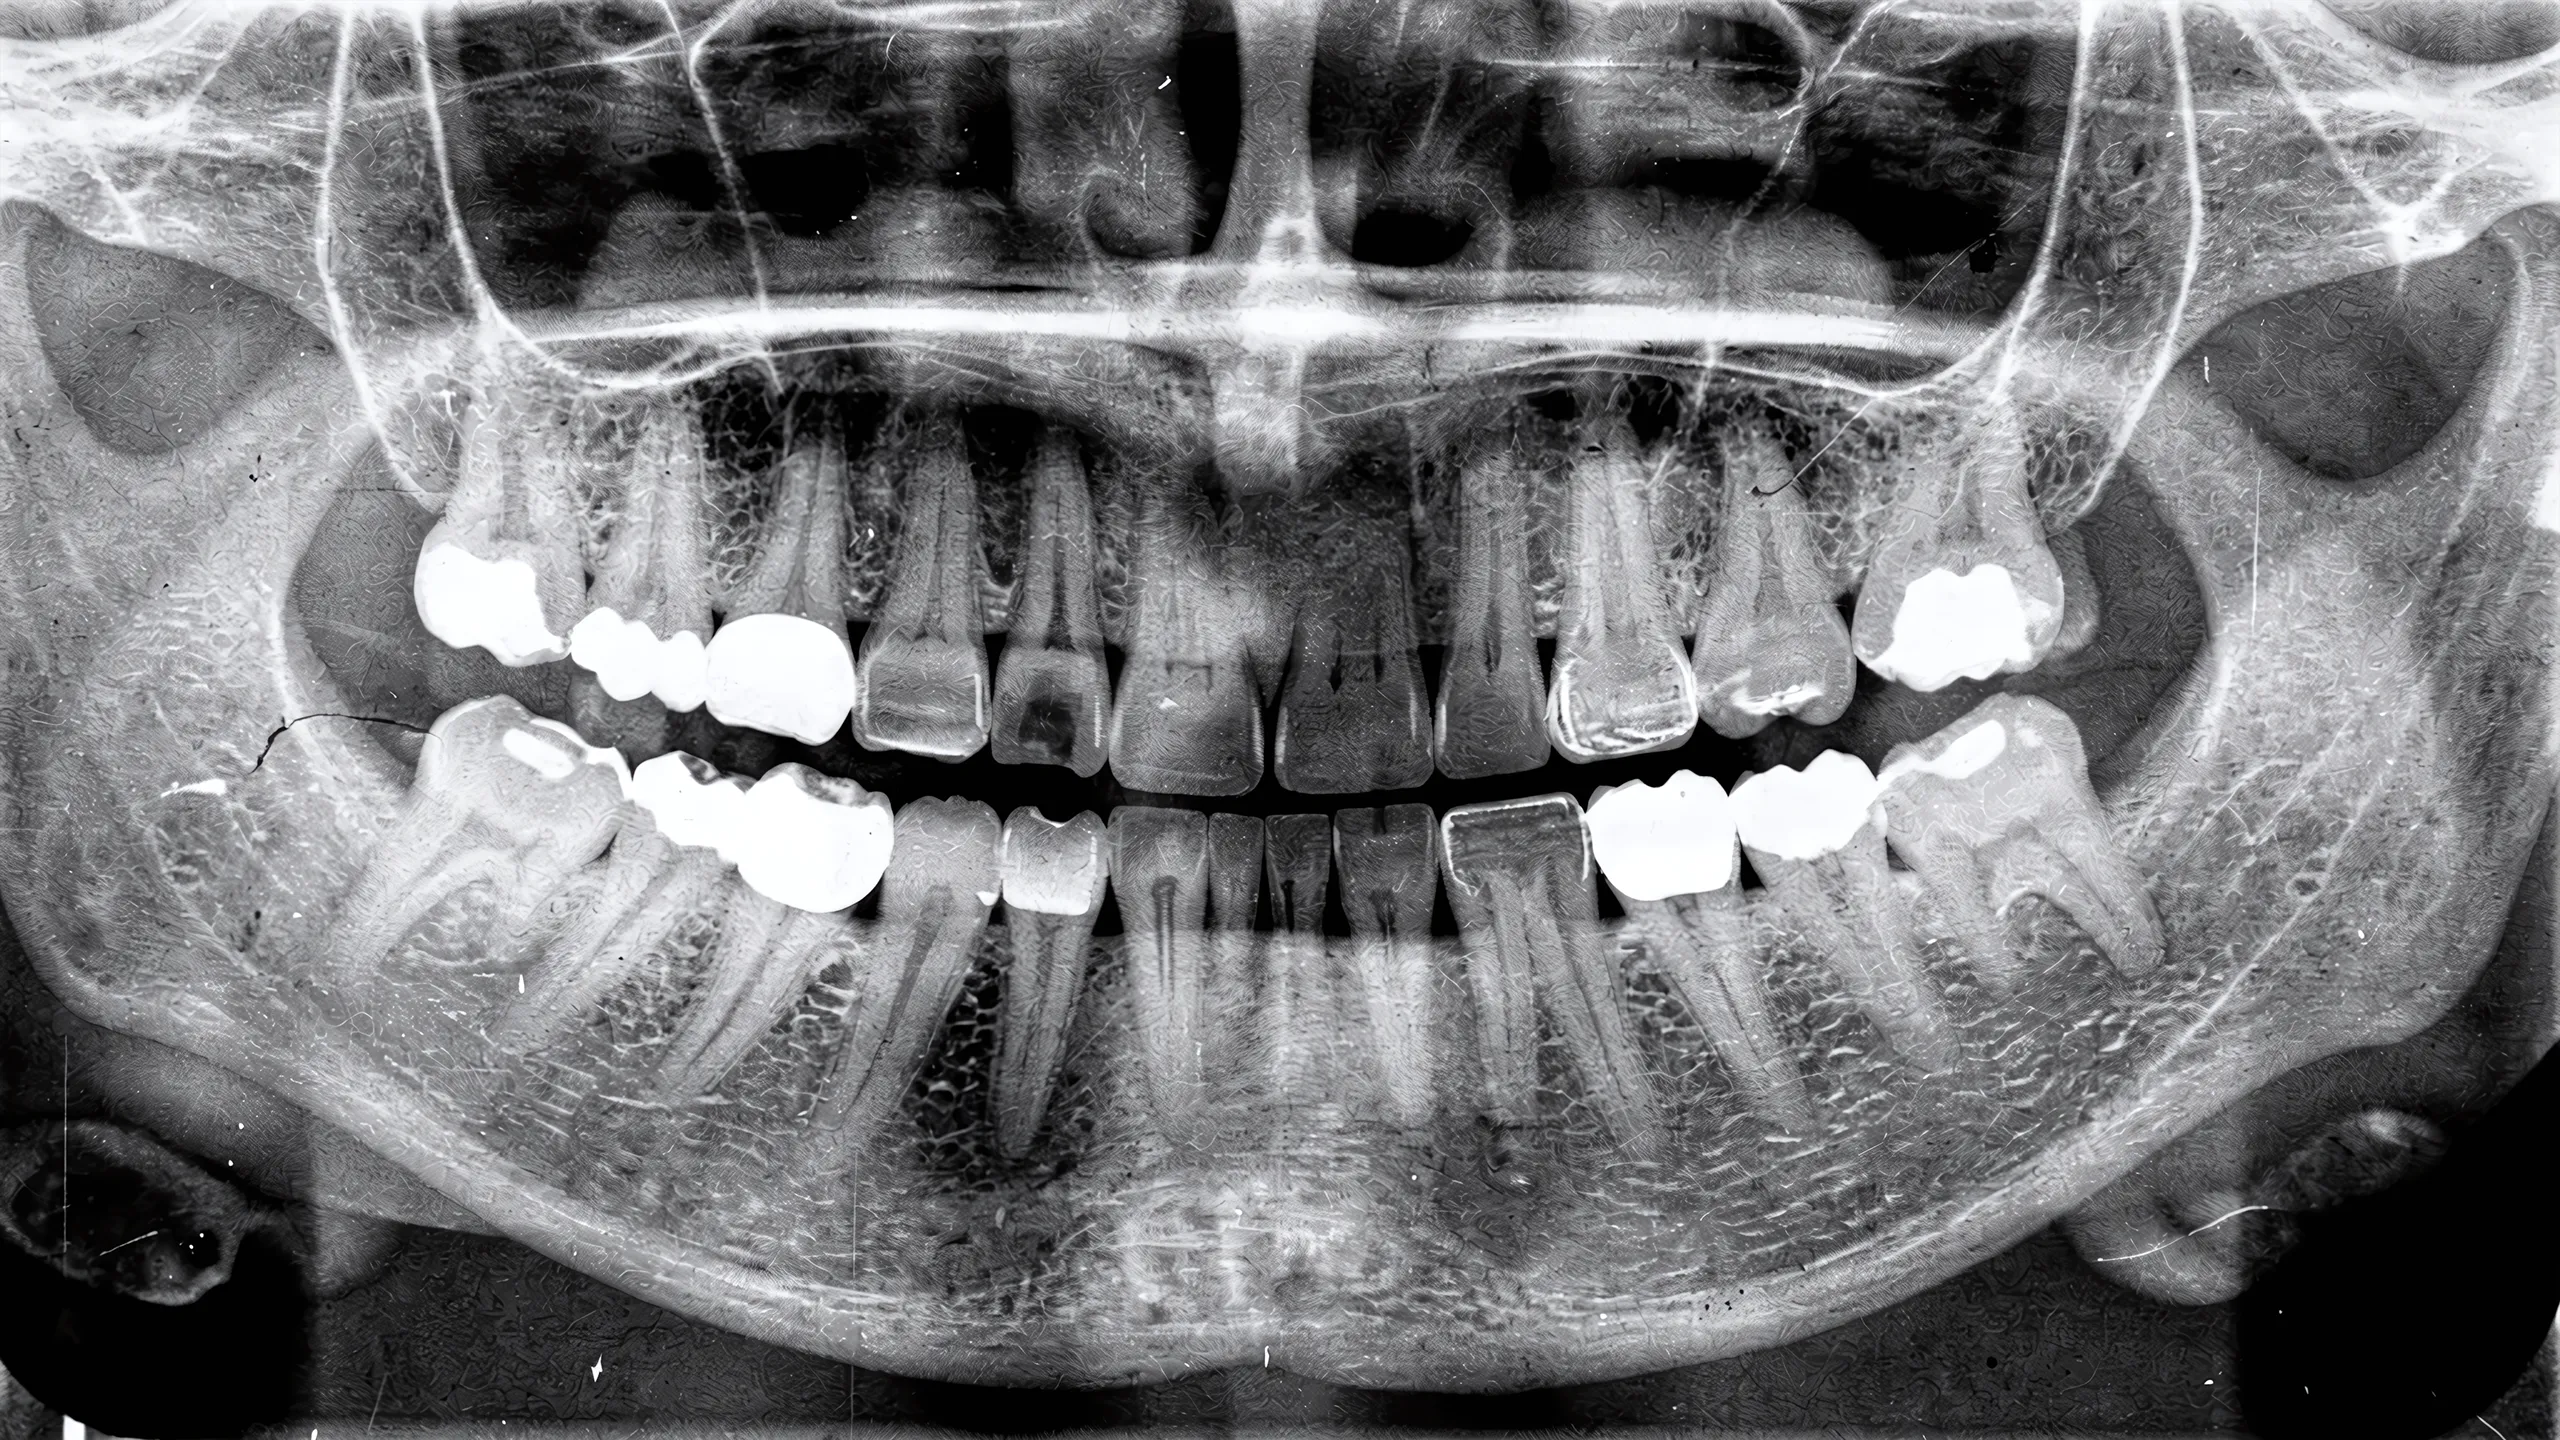

Проводится детальный осмотр, обязательным является выполнение компьютерной томографии (КТ). Анализируется состояние корня удаляемого зуба, объем и плотность окружающей кости, целостность костных стенок лунки, отсутствие активного воспалительного процесса.

Подбирается конструкция, диаметр и длина которой позволяют достичь стабильности в кости за пределами лунки удаленного зуба (на 3-5 мм в апикальном отделе и, при необходимости, в лабиальную или небную стенку).